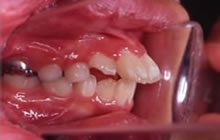

■1期治療終了時(8歳11ヶ月)

1期治療が終わりました。前歯のかみ合わせは適正になりました。唇は少し閉じやすくなりましたがまだ上下口唇は突出しています。